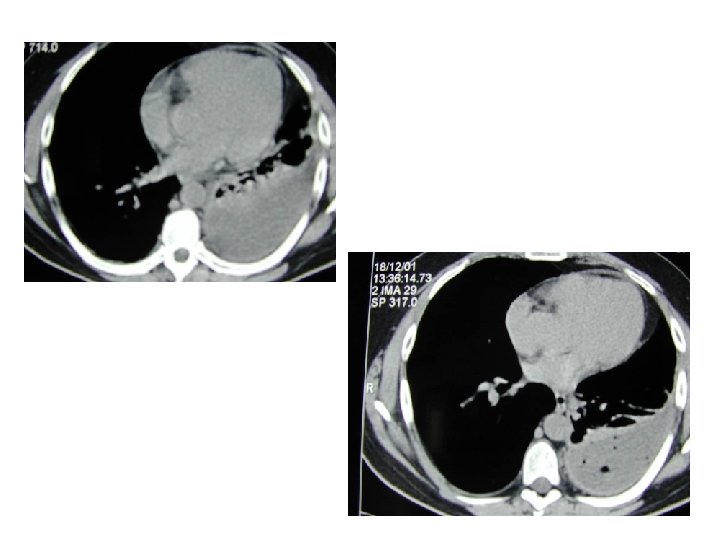

Cas clinique 1 • • Homme 65 ans suivi pour BPCO Retraité SNCF Tabagique Asymptomatique hormis BPCO

Cas clinique n° 2

• Quelques mois plus tard : AEG, douleur basithotacique droite, dyspnée • Épanchement pleural droit 3/4 de l’hémichamp

Quel diagnostic suspectez vous? Mésothéliome

Le mésothéliome • Exposition à l’amiante dans 80% des cas, parfois très ancienne ou indirecte • Diagnostic difficile : biopsies sous thoracoscopie • Parfois asbestose connue avant • Traitement curatif rare et lourd / Palliatif – – Symphyse pleurale Chimiothérapie Radiothérapie sur le trajet des drains / antalgique Évolution loco-régionale